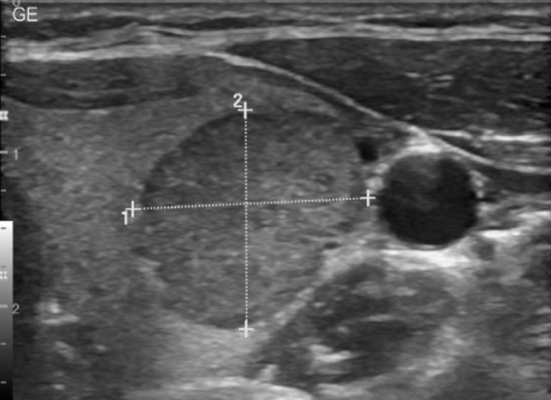

U tuyến giáp lành tính thường phổ biến ở nữ giới, khiến người mắc cảm thấy khó chịu hoặc thậm chí khó thở hay nuốt nghẹn. Để hiểu rõ hơn về quá trình điều trị u tuyến giáp lành tính hiệu quả, cùng MỔ TUYẾN GIÁP theo dõi bài viết...